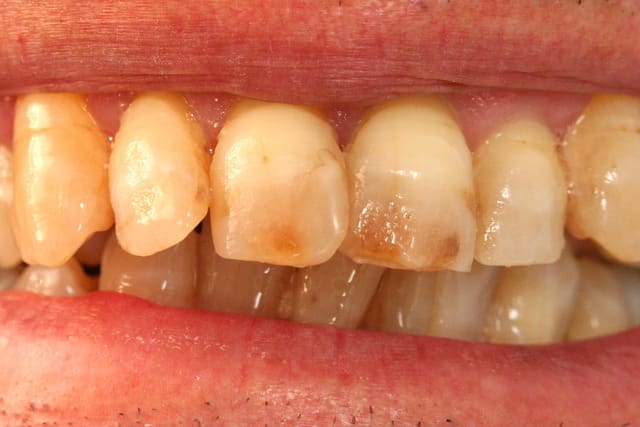

R29 uvltlt - Eugenol

R49 enunsh - Eugenol

R22 vkd0tr - Eugenol

R23 pmkimv - Eugenol

R26 gr1kkt - Eugenol

R34 w9wpow - Eugenol

Img 0052 dkvbyu - Eugenol

Leandro

28/02/2013 à 21h54

Joli travail!